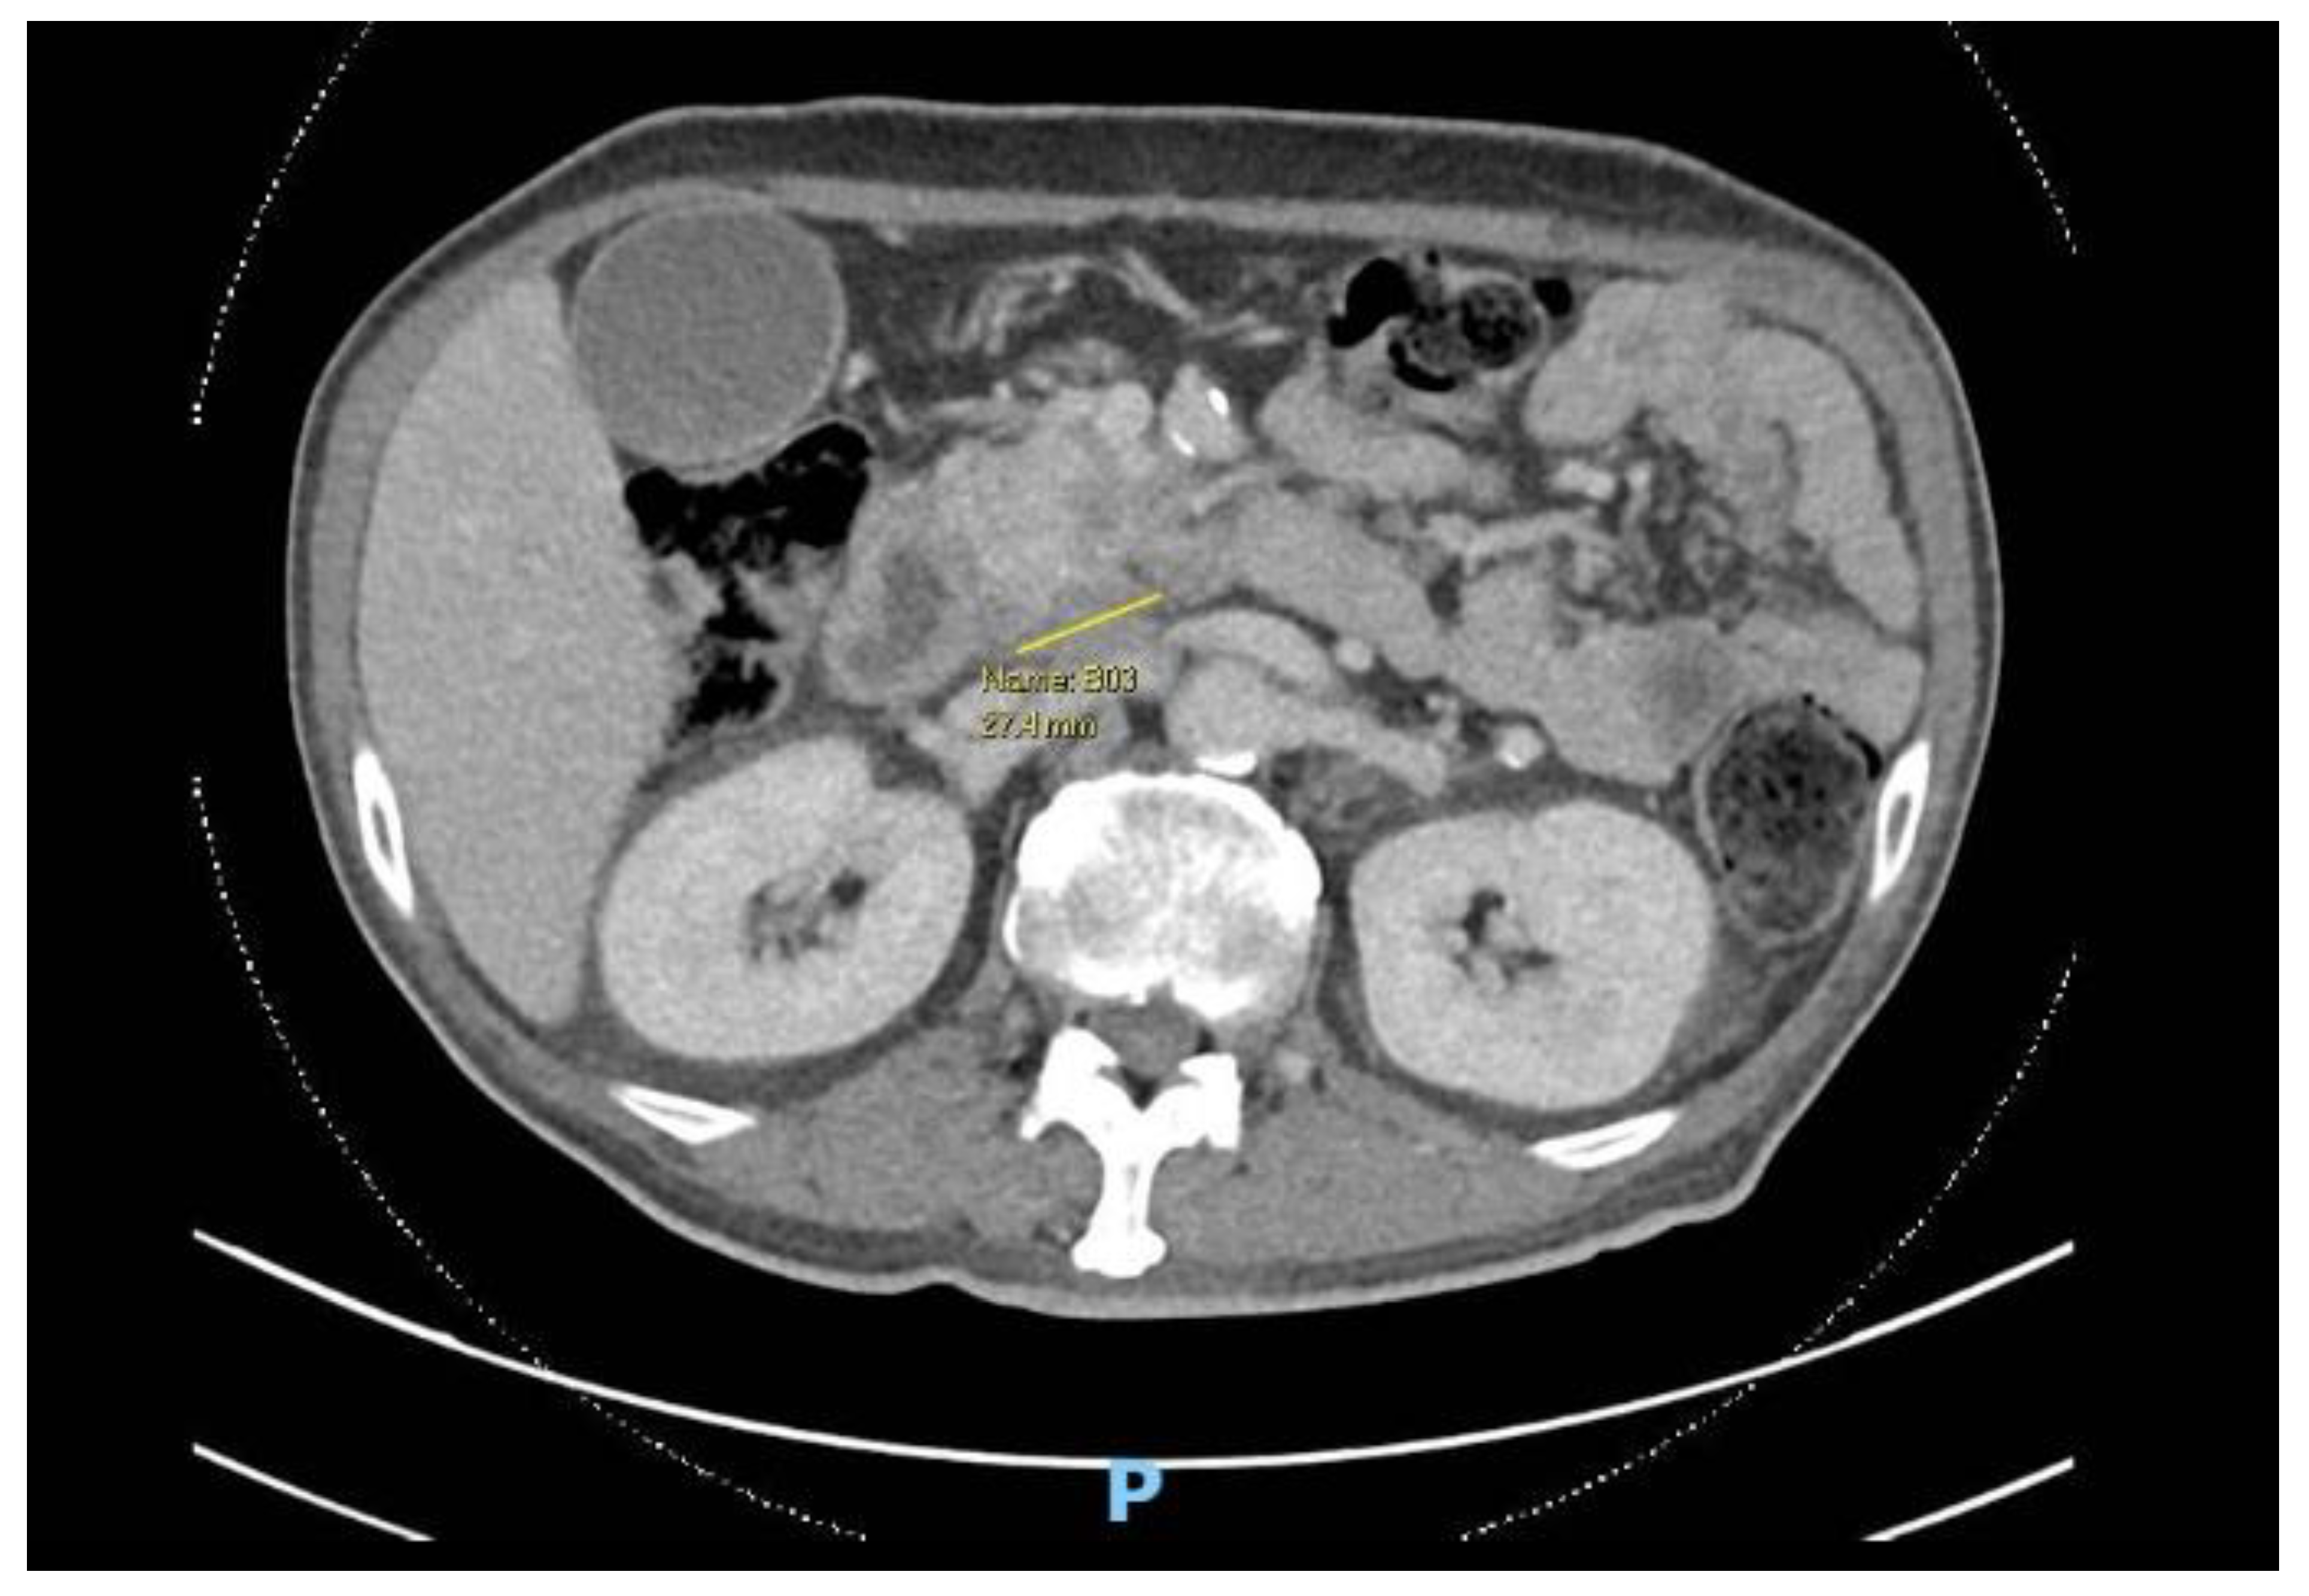

The first patient is a 60-year-old male, driver, smoker with poorly controlled diabetes, Chronic Kidney Disease (CKD), Ischemic Heart Disease (IHD) and newly diagnosed locally advanced borderline resectable head of pancreas malignancy with superior mesenteric vessel involvement.

Figure 1. Computed Tomography (CT) scan showing axial cut of pancreatic malignancy.

Preprints 147084 g001